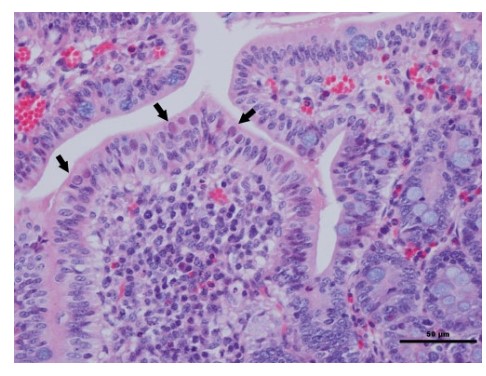

Bệnh tích vi thể: hình thành tiểu thể bao hàm, có thể quan sát được khi làm tiêu bản trực tiếp từ không tràng và hồi tràng. Kết quả gây bệnh thực nghiệm cũng cho thấy tế bào biểu mô của không tràng và hồi tràng bị phá hủy, trong khi đó lớp lông của ruột bị bào mòn. Màng não bị viêm, ống thận bị giãn nở. Phổi bị viêm biểu hiện: viêm kẽ phổi, thành phế nang dầy lên do tăng sinh tế bào vách ngăn và thâm nhiễm tế bào viêm.

Hình 2: Bệnh tích ở biểu mô ruột non của lợn bị nhiễm PAdV

Nguồn: Diseases of Swine, © 2019 John Wiley & Sons, Inc.